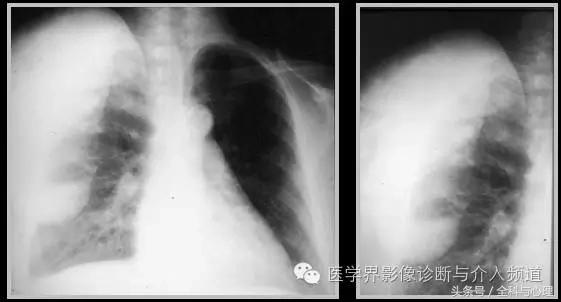

一、肿瘤样钙质沉着症

累及多个关节,范围较大,表现为多房囊状的高密度影。

原发性:罕见,多为家族性,多见于非洲裔美国人,钙磷正常。

继发性:多见于慢性肾功能不全患者。钙磷均有升高。

肿瘤样钙质沉着症